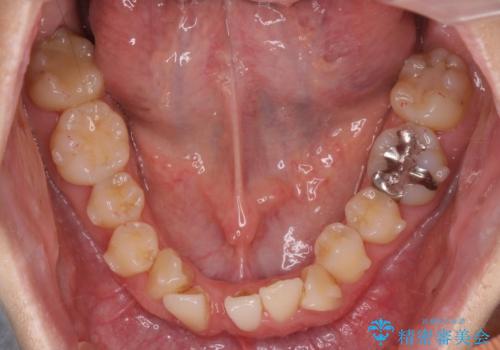

ねじれ・がたつきのある前歯を改善

- インビザライン +部分ワイヤー矯正

- がたつき・すれ違い、ねじれのある前歯の見た目、噛み合わせの改善を希望され来院されました。

4本の小臼歯抜歯を避け、下顎前歯の1本抜歯の極力少ない抜歯本数で審美的な歯並びを得る治療計画としました。

見た目の改善だけでなく、噛みやすくなったことにも満足いただくことができました。